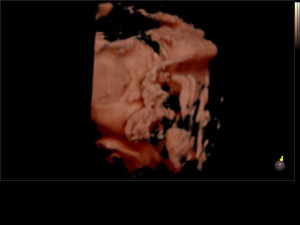

Gravidanza

Dottor Giuseppe Luzi accompagna la vostra gravidanza passo per passo, dall'assistenza prenatale al momento del parto, dalle ecografie alle analisi di laboratorio, alla cardiotocografia che vi permette di sentire i battiti del cuore del feti

il Dottor Luzi desidera che viviate la vostra gravidanza con serenità e felicità. Per questo vi fornisce una consulenza approfondita e mette a vostra disposizione tutta la sua esperienza.